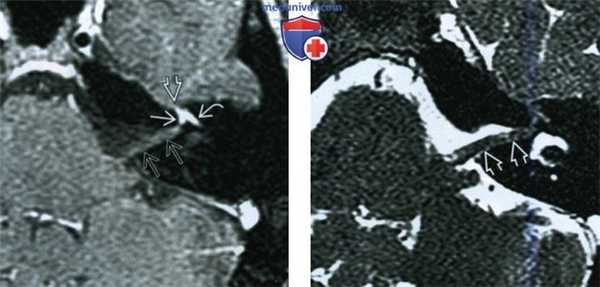

(Слева) МРТ, постконтрастное Т1-ВИ, режим подавления сигнала от жира, аксиальный срез: у пациента с выраженным длительное время сохраняющимся параличом Белла определяется интенсивное контрастирование лабиринтного, переднего барабанного участков лицевого нерва, а также коленчатого ганглия. «Хохолок» во ВСП простирается вдоль лицевого нерва, достигая внутреннего слухового отверстия, и визуализируется в виде менее интенсивного участка контрастирования.

(Справа) Тонкосрезовая (1 мм) МРТ, Т2-ВИ, режим подавления сигнала от жира, аксиальный срез: у этого же пациента определяется набухание лицевого нерва в области его канала.

(Слева) При аксиальной МРТ Т1 ВИ C+ FS у пациента с тяжелым параличом Белла, протекающим без ремиссий, определяется интенсивное контрастирование коленчатою ганглия, лабиринтной, передней барабанной части лицевого нерва. «Хохолок» идет по ходу лицевого нерва в ВСК в виде менее выраженного участка накопления контраста, достигая слуховою отверстия.

(Справа) При аксиальной тонкосрезовой (1 мм) МРТ Т2 ВИ FS у этою же пациента в ВСК визуализируется отечный интраканаликулярный сегмент лицевого нерва.